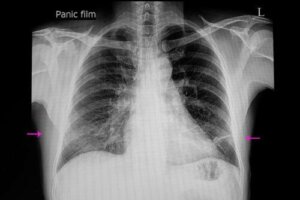

Niedodma – rozpoznanie

Techniki te obejmują tomografię komputerową, bronchoskopię, ultrasonografię i pulsoksymetrię. W rzeczywistości bronchoskopia pozwala na obserwację niedrożności, a nawet eliminację zatoru.